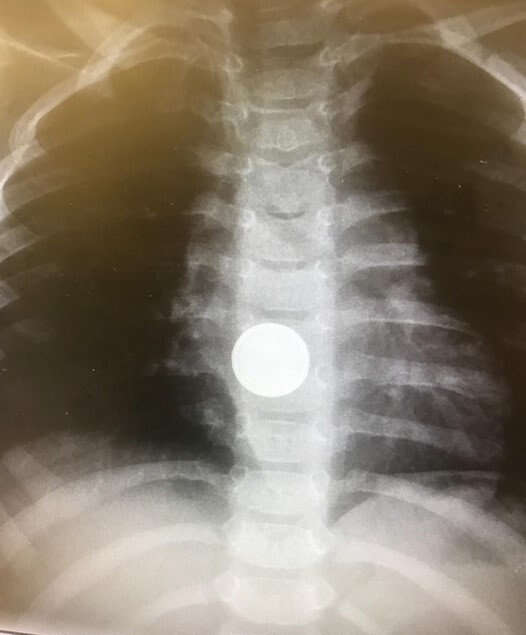

מה חדש? סוללה בדבש: בליעת חפצים קטנים על ידי פעוטות היא אחד הסיוטים של כל הורה, ובפרט בליעה של סוללות. הן עלולות להתפרק בדרכי העיכול ולגרום כווייה כימית ואף נזקים פנימיים לרקמות, בשל המוליכות שלהן.

בבית החולים שערי צדק גיבשו הנחיה מפתיעה שעשויה להמתיק מעט את המצב, ולא רק בראש השנה: לילדים מעל גיל שנה, שבלעו סוללה, יש לתת דבש מייד, על מנת לעכב ואף למנוע התפתחות של סיבוכים, זאת במקביל לפינוי מהיר אל בית החולים.

ההנחיה גובשה בעקבות פרסום מאמרים מקצועיים ומחקרים מהעת האחרונה, שהראו כי אכילת דבש מייד לאחר בליעה הסוללה עשויה לעכב היווצרות של כוויות כימיות, כיבים ופגיעה ברקמות, שנוצרים בעקבות המוליכות החשמלית של הסוללה והמגע ההדוק שלה עם דפנות הוושט. ההנחיה החדשה ממליצה להתחיל את הטיפול כבר בבית, במתן הדבש, ולגשת מייד למיון לקבלת טיפול בסמיכות לאירוע, כדי למנוע נזקים פנימיים קשים.

בשערי צדק מדגישים כי מתן דבש לתינוקות מתחת לגיל שנה אינו מומלץ גם במקרה של בליעת סוללות, משום שהוא עלול לגרום שיתוק נוירולוגי. לפי ההנחיה בשערי צדק, כל פעוט מעל גיל שנה יקבל 2-1 כפיות דבש בכל חמש דקות לאחר שבלע סוללה, עד להוצאתה דרך הלוע או בניתוח.

"בליעת סוללה על ידי ילד היא לא אירוע נדיר", מסביר ד"ר אורן לדר, מומחה בכיר בגסטרו־ילדים ואחראי על פעולות אנדוסקופיות בילדים בשערי צדק, "סוללה היא אחד הגופים הכי מסוכנים, והנזק עלול להיות קטלני. הדבר הקריטי ביותר הוא לשלוף את הסוללה כמה שיותר מהר. ועד שמגיעים לבית החולים אנו ממליצים לתת דבש להפחתת הנזק".